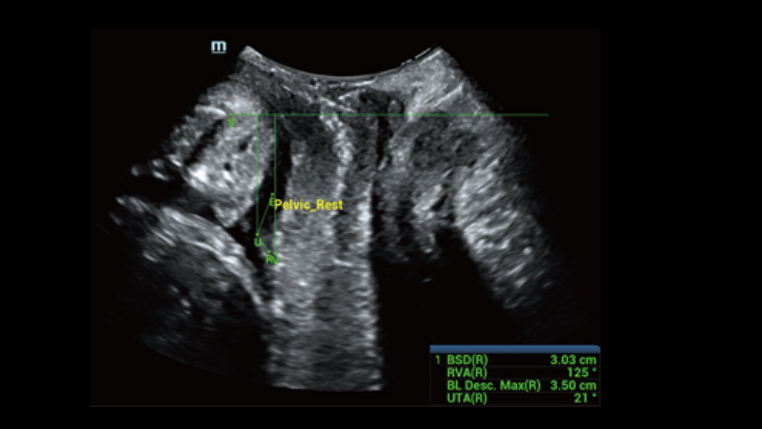

Natural touch Elastography provides multiple relative strain and stiffness parameters of breast, cervix, uterus and ovary lesion. With excellent sensitivity and stability, it provides further diagnostic information for more challenging demands.

A simple and well-tolerated ultrasound procedure used to assess the patency of the fallopian tubes, as well as detect abnormalities of the uterus and endometrium.